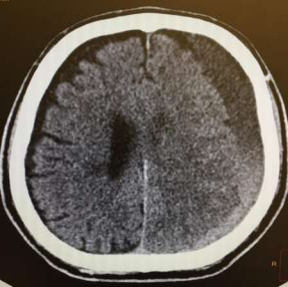

Radiology

Fig 1,2,3,4,5,6,7,8,9,10,11,12,13,14,15

Thirty eight out of Eighty-two patients were treated conservatively and were studied (25 men; 13 females, mean age, 64.8 years). The average thickness of the hematoma was 18 mm, the mean midline shift was 4.7 mm, and the average attenuation value of bleed on computed tomography scan was 33.5. Thirty-eight were treated successfully with steroid treatment, whereas 44 patients required surgery. The female gender, less midline shift, less density (Hounsfield units) was noted to be associated with successful medical treatment. We propose a grading based on the total score given to the midline shift and density.

Figure 1

Figure 2

Figure 3

Figure 4

Figure 5

Figure 6

Figure 7

Figure 8

Figure 9

Figure 10

Figure 11

Figure 12

Figure 13

Figure 14

Figure 15